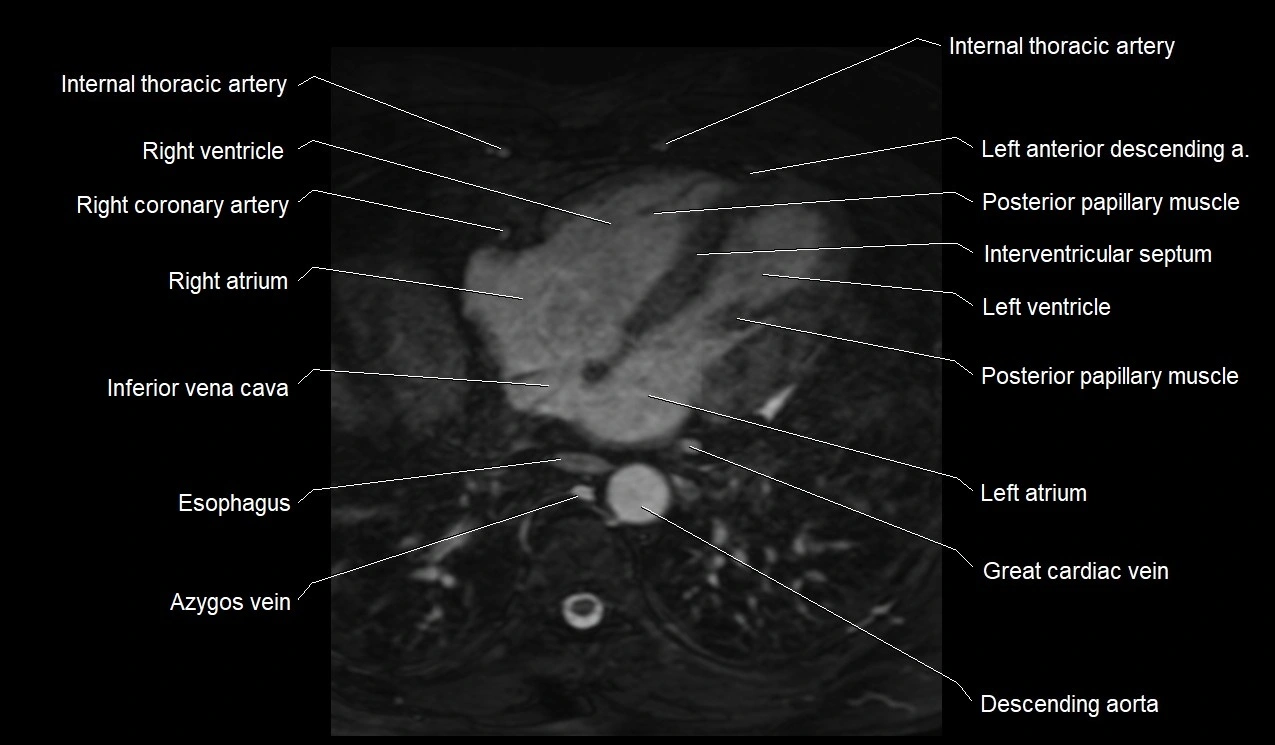

MRI image